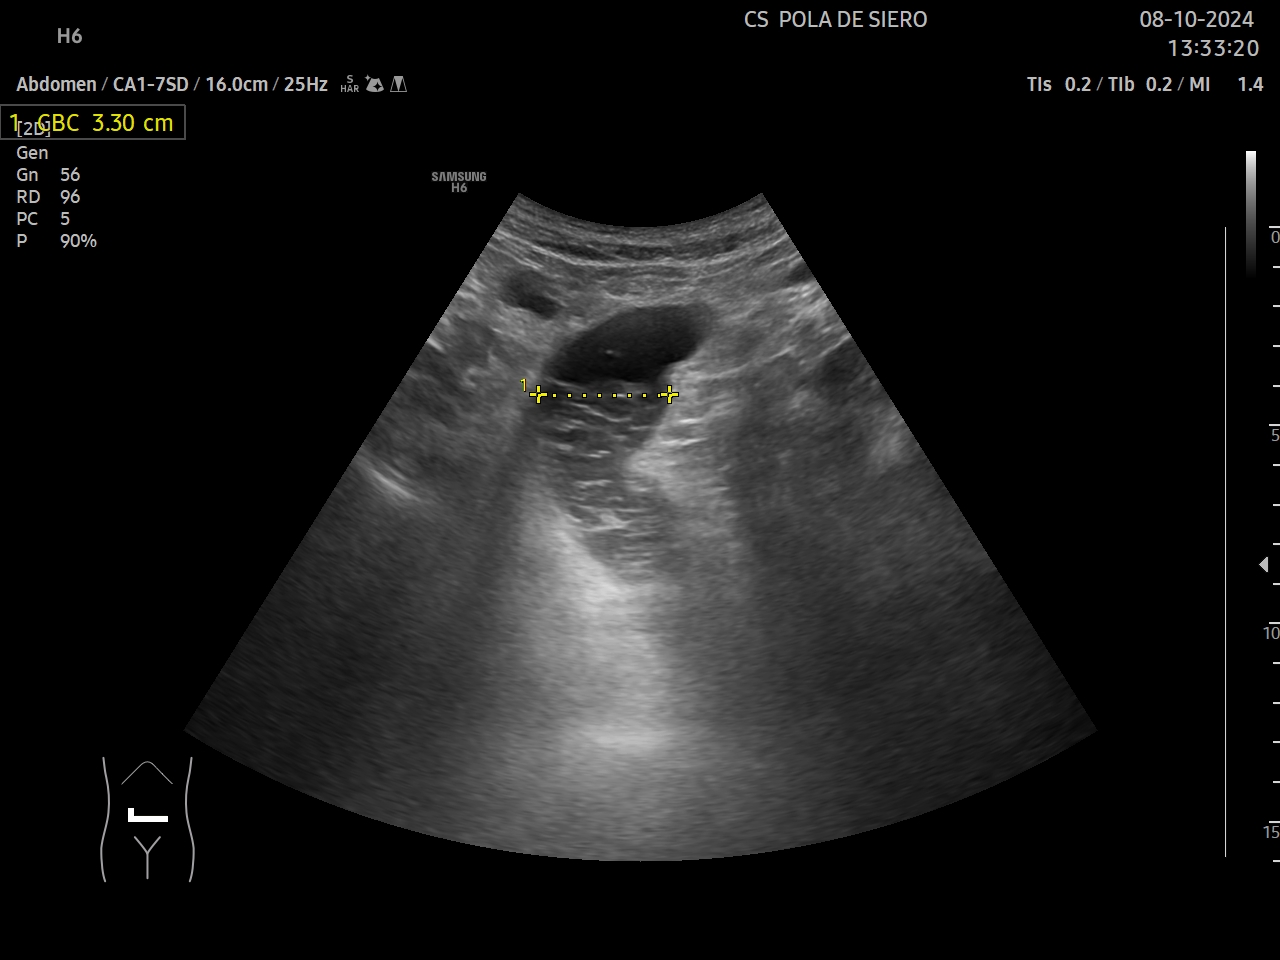

Hígado, vesícula, bazo, aorta y vejiga sin alteraciones significativas. Poliquistosis renal. No líquido libre. Se objetiva en un corte transversal en mesogastrio un asa intestinal dilatada de 3,3 cm, con muy escaso peristaltismo y objetivándose en su luz un nivel con una zona anecogénica superior y una zona hiperecogénica y heterogénea inferiormente.